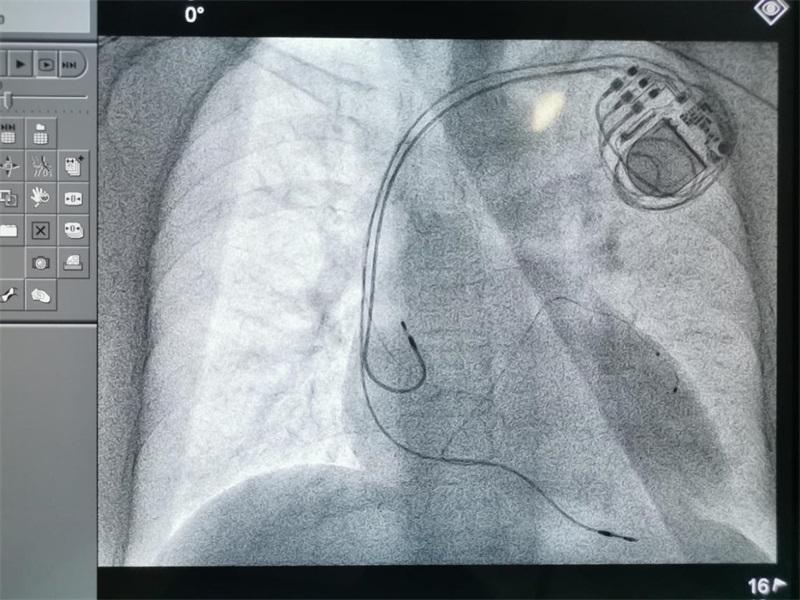

9月8日,南昌大學一附院心內科團隊為一名高危心力衰竭患者完成3D打印心臟模型指導下心臟再同步化治療(Cardiac Resynchronization Therapy,CRT)植入術。手術由王夢洪教授、彭景添教授、彭小平教授共同完成,該手術的成功開展,標志著該院院心內科治療技術再上新臺階。

術前,彭小平教授積極與影像科聯系、溝通,根據患者心臟CT圖像三維重建,通過3D打印技術,立體展示冠狀靜脈各分支以及心腔的空間結構,重建帶有冠狀靜脈分支的心臟立體模型,精確指導左、右心室電極、心房電極植入位置。手術過程中,術者在3D打印心臟模型精準指導下,將左室冠狀竇電極精準定位于冠狀靜脈左室外膜面分支,右室螺旋電極及心房電極分別定位于右室心尖部及右心耳,最后連接起搏脈沖發射器。因有了3D打印心臟模型的指導,手術較平時手術較少了近30分鐘。

該院心內科彭小平教授等人的最新研究發現,左、右心室電極植入位置間距離與CRT效果相關,CRT術中左、右心室電極植入位置越大,相應臨床效果越佳,左、右心室電極植入位置間距離是 CRT 效果獨立影響因素,此項研究成果獲2019年我院臨床優秀新技術一等獎。但是電極在冠狀靜脈分支、心室、心房的精確定位是影響CRT手術效果的重要因素,特別是如何在術前重建冠狀靜脈竇及其分支走形顯得尤其重要。

“3D打印心臟模型不僅可以重建心房心室,而且可以清晰顯示心臟冠狀竇及其分支血管的走形,為術中尋找合適的電極位置提供了極大的幫助,將有助于縮短手術時間,提高手術的安全性和成功率,提高術后CRT反應性及療效。”彭小平教授介紹道。

據鄭澤琪教授介紹,心臟再同步化治療(CRT)又稱雙心室起搏,是在傳統起搏基礎上增加左心室起搏,通過雙心室起搏的方式,治療心室收縮不同步的心力衰竭患者。心臟再同步化治療可改善患者的心臟功能,提高運動耐量以及生活質量,是心力衰竭治療史上一個里程碑式的突破。